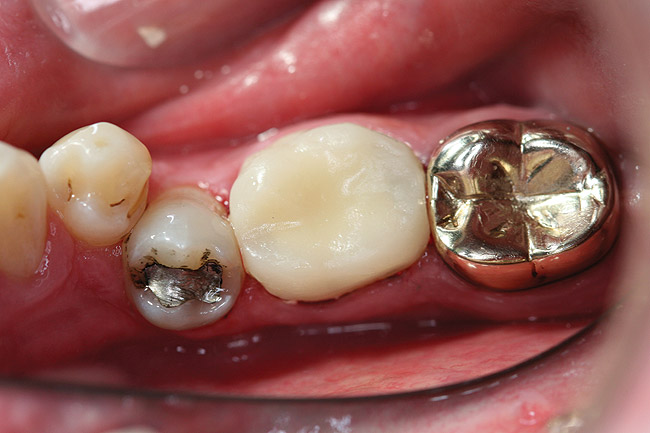

After dispensing a pea-sized amount on a mixing pad or 2X2 (the first amount may not be mixed completely) a fast-setting bis-acryl (the author used TemptationNOW for demonstration purposes) is injected into the matrix (Figure 3) and re-seated over the final preparation (Figure 4). With an initial cure (mouth removal time) of 45 seconds to 1 minute and a complete cure in 4.5 minutes, the overall temporization procedure time is reduced, and it allows for trimming earlier. The amount of bis-acryl injected into the matrix depends on where the gingival margin of the preparation is placed. As a general rule, if the gingival margin of the crown preparation is at the gingival tissues, fill the matrix slightly less than two thirds, and if subgingival, to the gingival margin of the matrix. If the matrix is overfilled, it may not seat completely, resulting in a high occlusion. It is better to under fill than overfill, as it is easier to add to the gingival than to correct a high occlusion. If the assistant wants to guarantee that this does not occur, a small triangular vent can be cut into the matrix material with a #15 Bard Parker blade leading from the gingival margin out through the bottom of the matrix, creating a spillway for the excess. Figure 5 shows the interior and margins of the temporary created for this clinical case. Figure 6 and Figure 7 show a temporary from another patient demonstrating the small amount of gingival flash that is routinely created with this technique. This minimizes the amount of finishing required, as compared to many other temporization techniques. The small amount of flash can be removed with a disc (Figure 8), but the author finds that pointed trimmers are faster, easier to use, and to control (Figure 9).

Figure  5  The interior and margins of the temporary created for this clinical case.

Figure 5